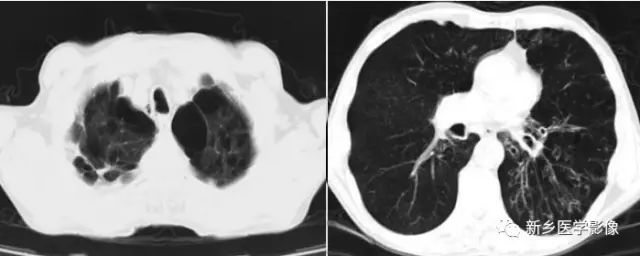

渗出性病变X线及CT图像

胸部X线正位片(a)示左肺纹理增多、模糊;CT肺窗(b)和纵膈窗(c)示两下肺片状高密度影,边缘模糊。

右肺下叶实变CT图:显示空气支气管征(↑)